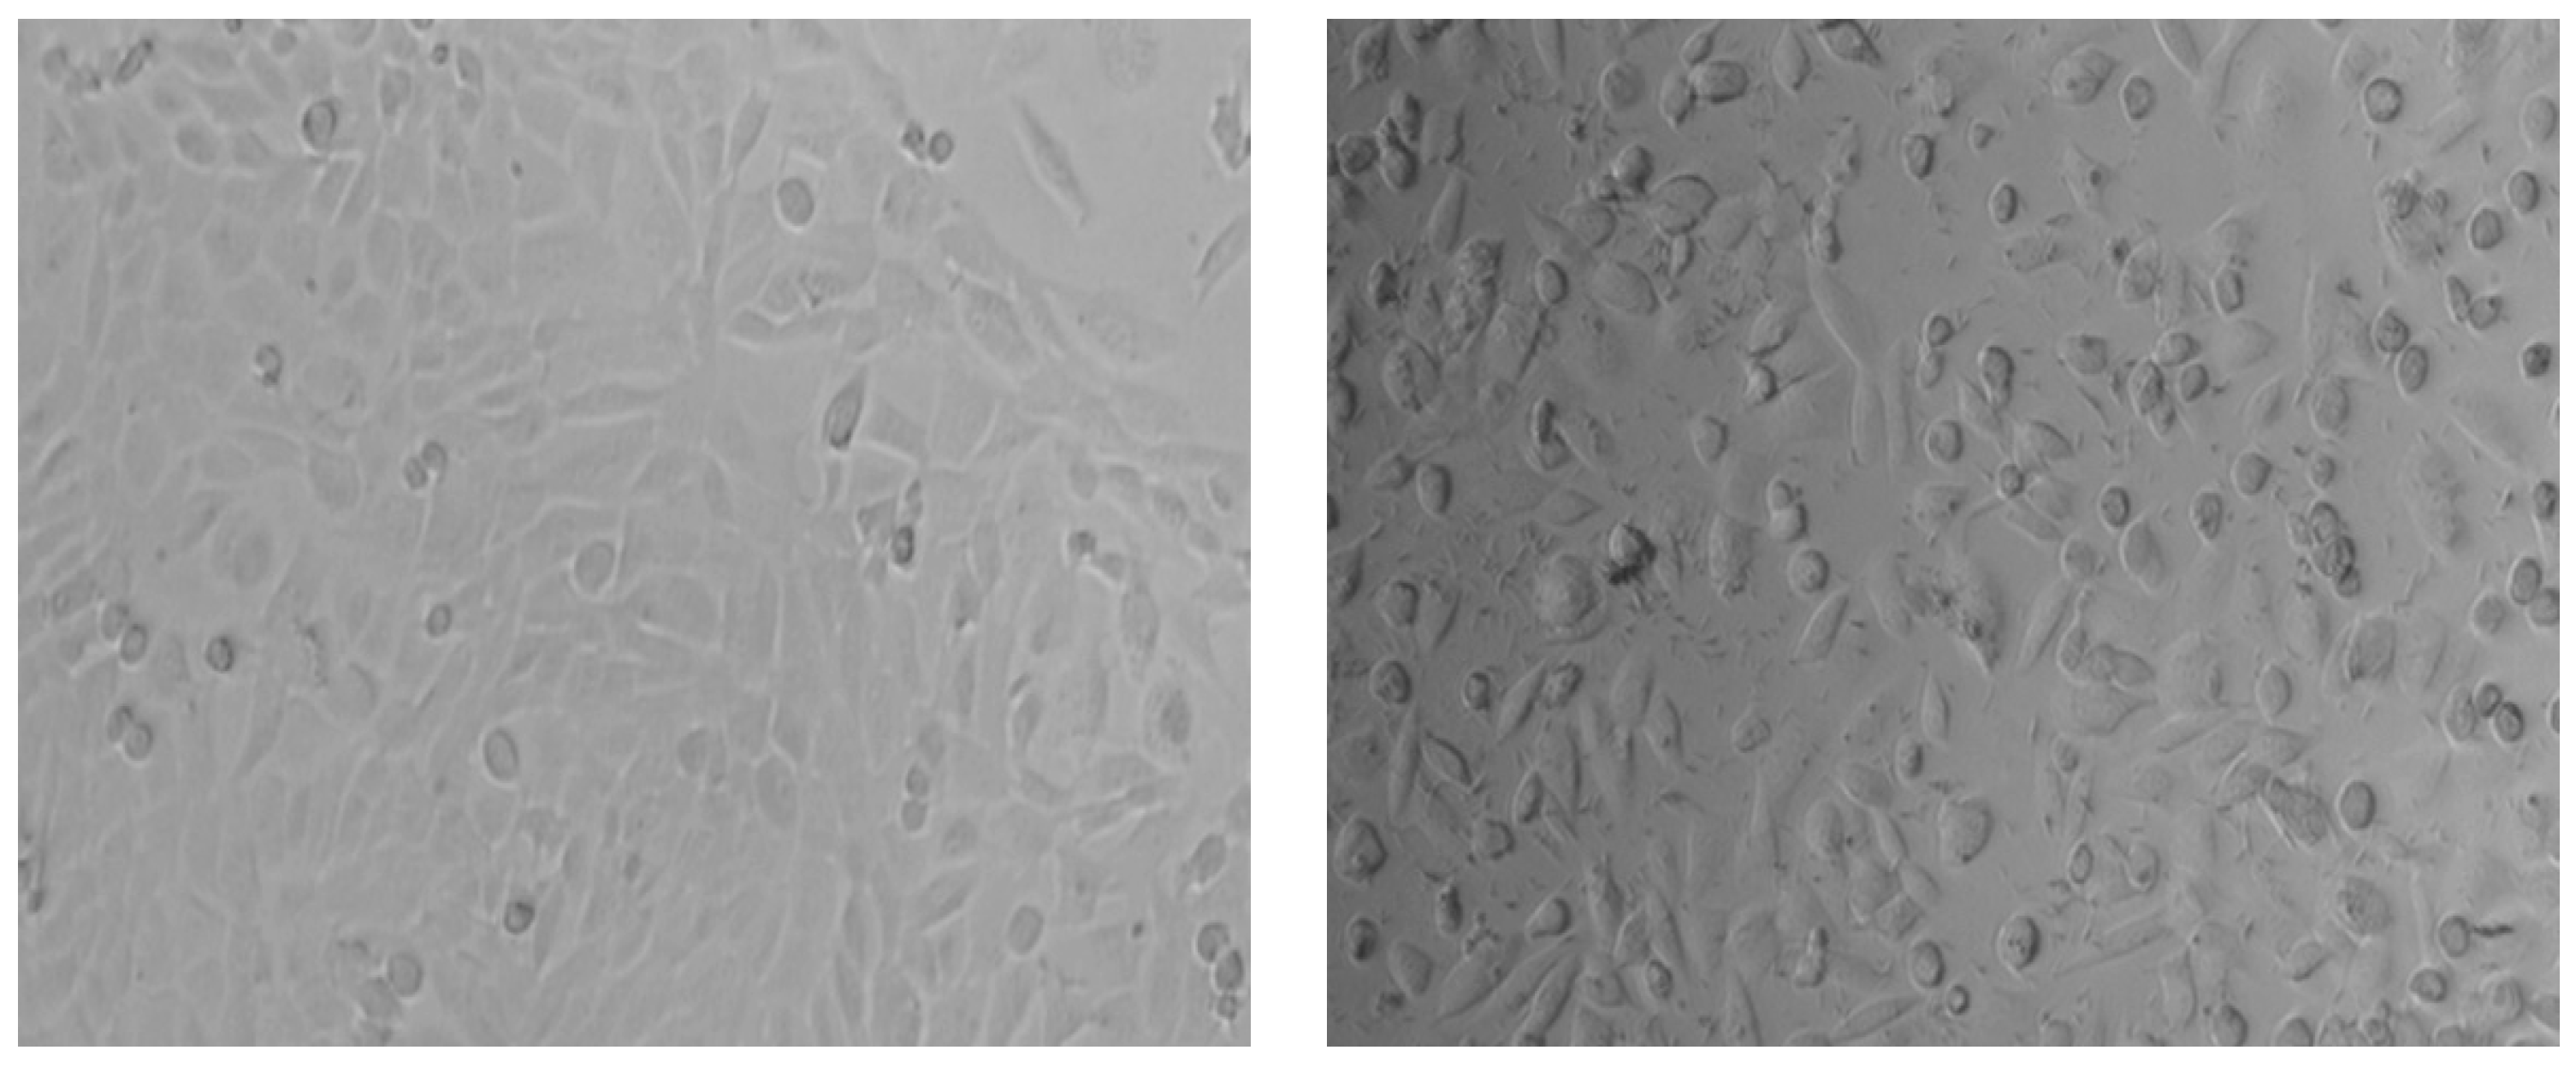

2.2. In Vitro Cell Culture Cytotoxicity Testing: Viability and the Micronucleus Test

2.2.1. Determination of Viability

3.1. In Vitro Cell Culture Cytotoxicity Testing: Viability and the Micronucleus Test

3.1.1. Viability Assay (MTT)